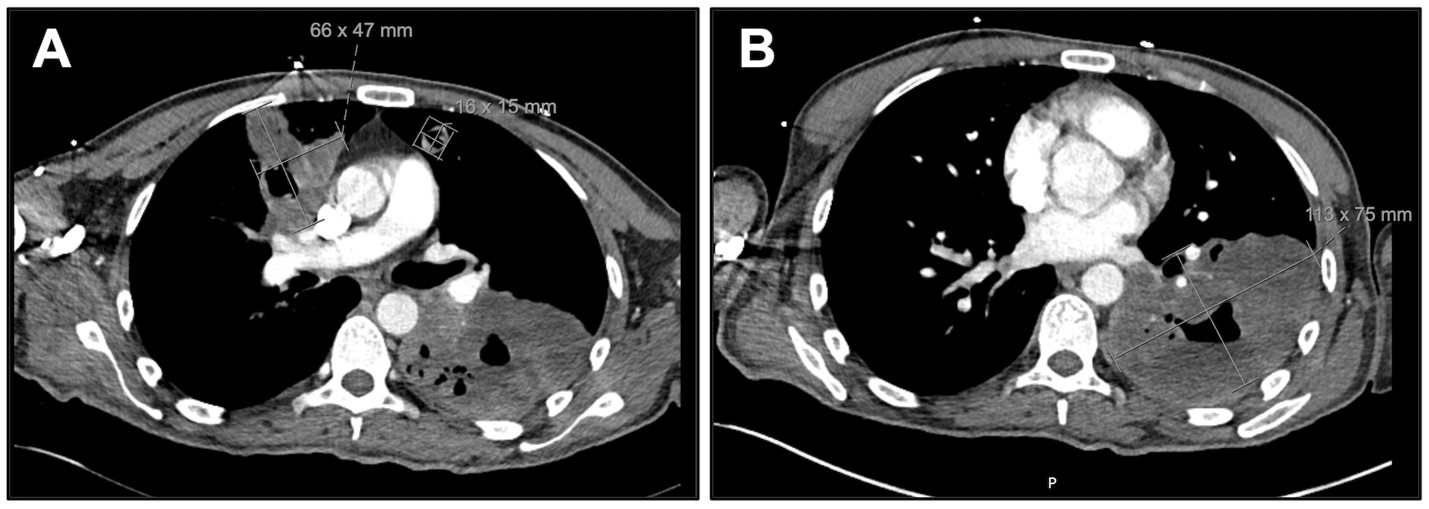

Upon evaluation, he reported epistaxis, bilateral eye irritation, impaired hearing, and enlargement of his ulcerative back lesion. Initial urinalysis revealed proteinuria (46 mg/dL; ~800mg/day; protein/creatine ratio 0.84) and hematuria (55 RBCs/HPF), concerning for nephritis, with a normal serum creatinine (0.77 mg/dL) and estimated glomerular filtration rate (98 mL/min/1.73m2). A repeat thoracic CT scan re-demonstrated the cavitary lesions with an interval size increase (Figure 2). Nasal endoscopy demonstrated multiple nasal septal perforations, and otoscopic evaluation revealed bilateral tympanic membrane perforations. Following admission, the patient began experiencing burning bilateral foot and hand pain accompanied by evolving petechiae, which erupted two days later into erythematous and violaceous palpable purpura and vesicles (Figure 3A). Biopsy of purpura demonstrated findings consistent with small-vessel vasculitis (Figure 3B). Further examination revealed pink conjunctival lesions as well as white subretinal and choroidal lesions (Figure 3C) and strawberry gingivitis (Figure 3D). Biopsy of the ulcerative lesion demonstrated a mixed perivascular and interstitial mixed inflammatory infiltrate, potentially consistent with pyoderma gangrenosum.